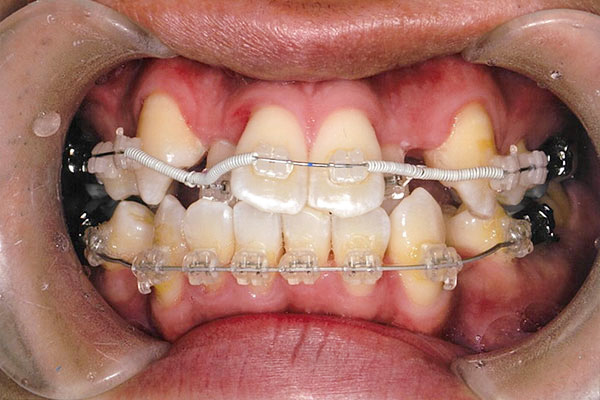

症状八重歯+二重歯列による噛み合わせ不具合

抜歯あり

1年5ヶ月後